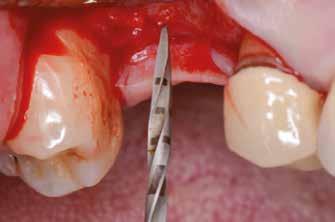

(2. ábra). A lágyszövetek értékelése Seibert szerinti I. osztályú csontdefektust állapított meg (3. ábra), ezért a beavatkozáskor palatinális „tekercslebenyt” preparáltunk (palatal roll flap), és implantációt végeztünk, hogy kompenzálni tudjuk a bukkális lágyszövet-behúzódást. Megmértük a vertikális lágyszövetvastagságot, és úgy terveztük, hogy a szubkresztális implantátum beültetése összhangban legyen a biológiai szélesség kialakulásával a transzgingivális gyógyulási periódus alatt (4. ábra)

Sebészeti eljárás

Az eljárást helyi érzéstelenítés mellett végeztük (4%-os articaine-hidroklorid 1:100 000 adrenalinnal). Papillakímélő, U alakú palatális bemetszést végeztünk, teljes vastagságú nyálkahártyalebeny preparálás történt, a lebenyt bukkálisan feltekertük (5. ábra). A lebeny bukkálisan feltekert részén de-epitelizációt végeztük el, amellyel kompenzálni tudtuk a bukkális lágyszöveti defektust. Szakaszos előfúrást végeztünk, és a bredent copaSKY 4x10 implantátumot 30 Ncm behajtási nyomatékkal helyeztük be (6. ábra). Az implantátumot 1 mm-re szubkresztálisan helyeztük be, hogy később szélesebb emergenciaprofilt tudjunk kialakítani (7. ábra). Az egyedi ínyformázó úgy készült, hogy kompozitot vittünk fel a titánbázisra, és így formáztuk a lágyszöveteket a transzgingivális gyógyulási fázis során (8. ábra). Az egyéni ínyformázó tulipán formájú, hogy kialakítsa a kívánt emergenciaprofilt. A lágyszövetet feszülésmentesen zártuk #6/0 nem felszívódó, monofil fonallal (Optilene, B. Braun Deutschland; 9. a–b. ábra). Posztoperatív röntgenfelvétel készült, ami alapján az implantátum a szomszédos fogakkal párhuzamos elhelyezést mutatott (10. ábra). Posztoperatív utasításokat adtunk a páciensnek a műtéti terület körüli szájhigiénia fenntartása érdekében. A beavatkozást követő egy héttel a varratokat eltávolítottuk, és a kezelt terület kielégítő gyógyulást mutatott (11. ábra). A 4 hónap utáni késleltetett terhelést a páciens kívánsága szerint terveztük.

1. ábra: Műtét előtti fogászati panorámafelvétel, amelyen a hiányzó felső állcsont jobb első premolárisát és a szabad véggel rendelkező hidat láthatjuk. — 2. ábra: Az implantátum méreteinek megtervezése CBCT-vel. 3. ábra: Bukkális lágyrészdefektus. — 4. ábra: A biológiai szélesség értékelése a vertikális lágyszövetvastagság alapján. 5. ábra: Palatinális „tekercslebeny” – Palatal roll flap. — 6. ábra: Bredent medical copaSKY 4x10 implantátumbeültetés. 7. ábra: Szubkresztális implantátumbeültetés a várható biológiai szélességnek megfelelően.